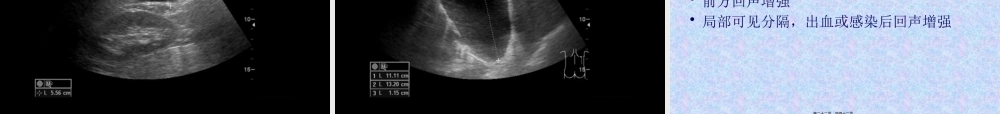

2、本站所有内容均由合作方或网友上传,本站不对文档的完整性、权威性及其观点立场正确性做任何保证或承诺!文档内容仅供研究参考,付费前请自行鉴别。